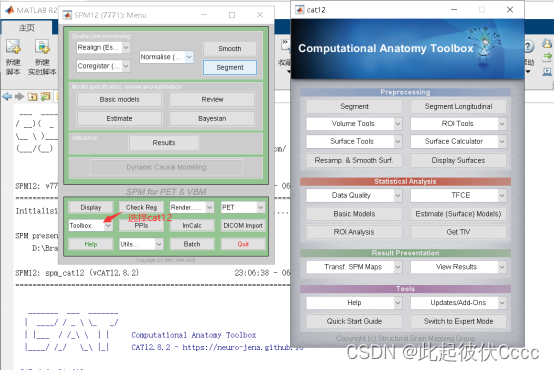

(1)运行Matlab2018a,在命令框中输入:spm敲回车,调用spm工具包。

(2)在SPM for functional MRI部分找到Toolbox,下拉找到cat12,点击打开cat12工具包,之后便会出现工具包cat12的操作界面,如下图:

(3)点击segment,进入如下界面: